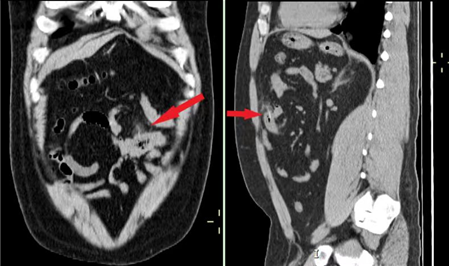

23岁小伙不慎吞咽鱼刺2天后腹痛入院,腹部CT图像上可见左下腹小肠内一细条状高密度异物(鱼刺)并部分穿破肠壁进入腹腔。